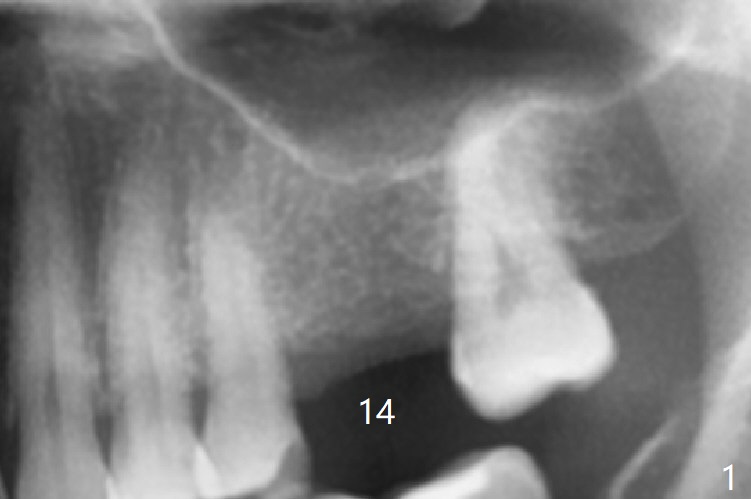

The guide is removed when the osteotomy at #14 (Fig.1 (8.45 mm bone height)) is finished in an under drilling manner in depth (Fig.2). The middle of the apical remaining bone is so thin (Fig.3 (white line representing the sinus floor)) that it can be pushed up like ping pong or eggshell (Fig.4 arrow). A 5x8.5 mm implant is placed with satisfactory insertion torque and depth, followed by insertion of a 6x3 mm healing abutment (Fig.5). There is mild resorption of the sinus floor distally 3.5 months postop, although the implant remains stable (Fig.6).